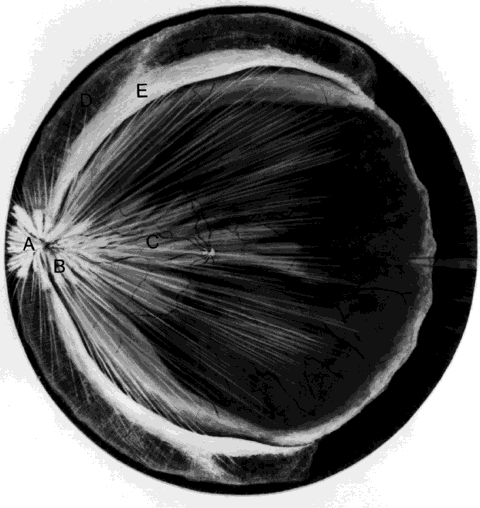

hemorrhage, retinal breaks, and retinal detachment. SUBLUXATION OR DISLOCATION OF THE LENS Minor degrees of subluxation should be suspected when phakodonesis or iridodonesis is noted. Zonular rupture is certain if there is vitreous prolapse into the anterior chamber. In the absence of cataractous changes and related visual impairment, treatment is not indicated. A subluxated, cataractous lens can be removed by aspiration-irrigation or phacofragmentation through a limbal incision, but complications may occur, including posterior dislocation of the lens or lens fragments, vitreous prolapse and incarceration, and vitreous aspiration with resultant vitreous base traction and retinal tear formation. Also, visualization of the anterior vitreous by coaxial illumination is poor compared with fiberoptic endoillumination. These problems make pars plana lensectomy an attractive alternative. Bimanual techniques permit fixation and simultaneous removal of the lens by the vitreous suction-cutter, if the lens is soft, or phacofragmentation if it is sclerotic (Fig. 1A). Posteriorly dislocated fragments can be removed safely, with minimal vitreous traction, using the same incisions and instruments (see Fig. 1B). With endoillumination, prolapsed and juxtalenticular vitreous is readily identified and excised with the vitrectomy probe. Without question, pars plana lensectomy is the preferred method for removing a completely dislocated lens. The technical aspects of dislocated lens and lens fragment removal are described elsewhere in these volumes. VITREOUS HEMORRHAGE Blood in the vitreous may come from tears in the iris, ciliary body, choroid, or retina. Hemorrhage from choroidal ruptures accumulates beneath the neurosensory retina; it then passes through the retina into the vitreous without necessarily causing a retinal break. Regardless, it is important to assume that a retinal break is present until proved otherwise. Vitrectomy is indicated for vitreous hemorrhage caused by ocular contusion when a retinal detachment is suspected because of sudden additional loss of vision, when a retinal detachment is detected through a window in the hemorrhage, when a large retinal break or retinal detachment is diagnosed by ultrasound, or when there is no improvement after a reasonable period of observation. Preoperative contact A-scan and B-scan ultrasonography is helpful for detecting posterior vitreous detachment and differentiating it from retinal detachment. It is dangerous, however, to rely completely upon the accuracy of ultrasound. The presumed posterior hyaloid should be approached with caution until it can be identified with certainty. A standard three-port vitrectomy technique is preferred for nonclearing vitreous hemorrhage. Initially, a central core of opaque vitreous is removed, beginning sufficiently close to the lens that the tips of the cutter and endoilluminator can be visualized. The excision is carried posteriorly, removing successive layers of hemorrhagic and fibrinous vitreous, until the anticipated plane of the posterior hyaloid is approached. A constant surveillance is maintained for a gray membrane containing radially oriented vessels (undiagnosed detached retina). A small opening is made in the detached posterior hyaloid, through which unclotted blood is aspirated by use of active suction from a soft-tipped cannula. Once the retina has been visualized, it is best to remove as much retrohyaloid blood as possible to prevent dispersion into the vitreous cavity with consequent loss of visual control. If the posterior vitreous cortex is not detached, it can be separated from the retina by gentle suction with a soft-tipped cannula at the edge of the optic disc. The elevated cortex is penetrated with a hooked needle or myringotomy blade, creating a window through which a pick is introduced to enlarge the area of cleavage. With the plane between hyaloid and retina established, the surgeon attempts to remove the entire cortical vitreous except for the firmly attached portion at the anterior vitreous base. Cortex that does not separate with gentle manipulation is isolated from surrounding vitreous to eliminate traction on the retina. It is important to remove the cortical vitreous from areas adjacent to retinal breaks. Failure to do so may result in subsequent tangential traction and retinal detachment. A scleral buckle should be considered if retinal breaks cannot be freed from surrounding vitreous cortex. The placement of sclerotomies close to the 3 o'clock and 9 o'clock positions facilitates maximal excision of the hemorrhagic anterior vitreous skirt, thereby improving visualization of the peripheral retina and pars plana. With use of coaxial illumination and scleral depression, the peripheral vitreous on the temporal side of the globe is trimmed with the cutter placed in the temporal sclerotomy, reaching both the superior and inferior quadrants, after which it is transferred to the nasal sclerotomy, and the process is repeated. The fiberoptic endoilluminator may damage the lens if used internally to illuminate the peripheral vitreous on the opposite side of the globe. However, the cone of light from the probe may be directed through the cornea to augment or replace the coaxial light source. Hemorrhagic retrolenticular vitreous can be stripped from the posterior capsule of the lens by gentle aspiration into the cutting port followed by withdrawal of the probe and simultaneous activation of the cutting mode. This technique is dangerous in young children because the retrolenticular vitreous is adherent to the lens, which is sufficiently pliable for aspiration into the port with consequent cataract formation. When the lens is clear, the process of removing peripheral and retrolenticular vitreous is less important than preserving lens integrity in most cases. It is important to expose the peripheral retina and vitreous base because most retinal breaks caused by ocular contusion are located in this area.2 All retinal breaks should be treated. Endolaser is used for posterior breaks, whereas peripheral breaks are treated with indirect laser assisted by scleral depression or transscleral cryoretinopexy. Cryotherapy is preferred when residual opaque vitreous partially obscures the targeted break. Encircling scleral buckles are not necessary after vitrectomy for nonclearing vitreous hemorrhage caused by ocular contusion when a clear view of the fundus periphery reveals no peripheral retinal tears or signs of traction, such as vitreous base avulsion. Similarly, the support of a buckle is usually not needed for treated retinal breaks without retinal detachment. A local scleral buckle should be used when there is residual traction on a posterior break. The peripheral retina should be supported by an encircling scleral buckle when traction on breaks in the oral zone persists or the periphery is poorly visualized because of residual opaque vitreous. RETINAL BREAKS Retinal breaks are created at the time of nonpenetrating blunt injuries3 in 10% to 20% of eyes.3–6 Retinal dialyses are most frequent2–6 and are most often found in the lower temporal (Fig. 2) and upper nasal periphery (Fig. 3).2 Large irregular breaks at the point of impact of blunt trauma are less common but are equally characteristic of nonpenetrating injuries (see Fig. 3).2,7,8 Horseshoe and opercular tears of the equatorial retina (see Fig. 3) are associated with the more characteristic breaks in 25% of eyes.2 Small round holes in atrophic retina at the point of traumatic impact and macular holes (see Fig. 3) are infrequently observed after ocular contusion.2,8 Prophylactic treatment of most traumatic retinal breaks is indicated. Breaks at the point of impact are one exception because they are frequently self-sealing. The surrounding necrotic retina and choroid often unite in a common scar without prophylaxis. It is wise, however, to treat these large tears when scleral depression reveals a slight elevation and movement of their edges and the surrounding retina. Traumatic macular holes also are not treated to prevent additional loss of central vision. They seldom cause retinal detachments when left alone. RETINAL DETACHMENT Although retinal breaks are produced at the time of injury, the retinal detachment may be delayed for months to years because the vitreous gel acts like a tamponade until liquefaction occurs.2 The detachment is typically shallow and slowly progressive because the large volume of vitreous gel in younger eyes prevents bullous retinal elevation as commonly seen in older patients with nontraumatic retinal detachments. Careful preoperative and intraoperative indirect ophthalmoscopy with scleral depression is the key to successful treatment of detachments caused by traumatic retinal dialyses. Small dialyses at the vitreous base borders are difficult to identify, particularly in the upper nasal quadrant where they frequently occur. Breaks of the pars plana epithelium, at the anterior vitreous base border, are less apparent than retinal tears at the posterior edge of the vitreous base. Small dialyses are closed by scleral depression, in which case they are more easily seen on the lateral slopes of the indentation than on its crest. Transscleral cryotherapy is diagnostically helpful. It is not unusual to discover breaks at the vitreous base border for the first time when the edges of the tear are whitened by freezing a suspicious area. It is prudent to treat the entire zone of vitreous base pathology with cryotherapy under direct visual control (see Fig. 3). In this way, treatment of all retinal breaks is assured. The anterior, posterior, and lateral limits of the treated zone are carefully localized and supported by a broad scleral buckle to relieve traction on the entire area. The posterior edge of the dialysis should fall on the crest of the buckle, which must be sufficiently broad to support the anterior edge as well, thereby preventing a recurrent detachment due to anterior leakage. Segments of grooved solid silicone tires are used together with an encircling band, which is positioned on a great circle of the globe to minimize anterior or posterior migration of the buckle. The band is tightened to ensure permanent indentation of the tire segment, but a high encircling buckle is avoided because it promotes posterior gaping or “fish-mouthing” of the dialysis. The band is anchored by a nonabsorbable mattress suture or scleral belt loop in each of the quadrants not occupied by the tire segment. The retinal detachment is often shallow. To avoid retinal perforation or incarceration, subretinal fluid is released through a sclerotomy in an area of sufficient retinal elevation determined by intraoperative indirect ophthalmoscopy with scleral depression. Viewed in profile, the scleral indentation helps gauge the distance between retina and retinal pigment epithelium. To avoid retinal incarceration and blowout, sclerotomies posterior to the buckle should be securely closed after the release of fluid, particularly if additional manipulation of the buckle or an intravitreal gas injection is anticipated. Retinal dialyses in the lower temporal quadrant are often very large, with gaping posterior edges located well behind the equator (see Fig. 2). They are caused by injuries impacting the lower temporal portion of the globe that result in the dissolution and disappearance of retinal tissue.8 In contrast to nontraumatic giant retinal tears with rolled-over retina, they respond favorably to scleral buckling without vitrectomy. A scleral buckle is indicated for smaller dialyses that can be closed with an explant of reasonable size. Very large breaks, as illustrated in Figure 2, are best treated with vitrectomy, gas tamponade, and laser, as recommended for nontraumatic giant retinal tears, rather than with a very large scleral buckle. Traumatic horseshoe and opercular tears are treated with scleral buckling surgery, as are similar nontraumatic retinal breaks. Likewise, traumatic macular holes in detached retina are managed by vitrectomy, internal drainage, and gas tamponade. The use of laser in such cases is controversial but is probably indicated for recurrent detachments and eyes with pre-existing poor central vision due to other traumatic macular damage. |